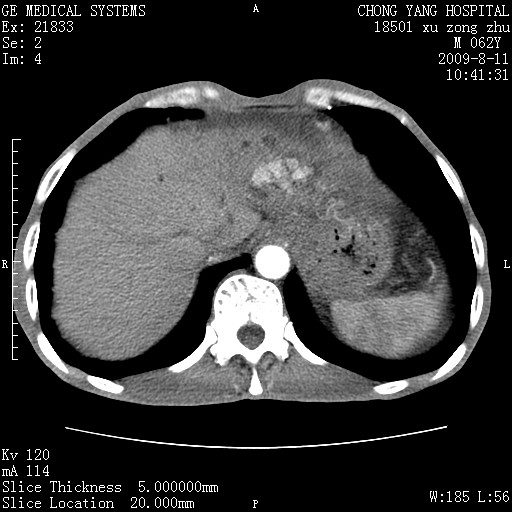

以下是引用杀毒软件在2009-8-11 16:35:00的发言:[br]肝内胆管扩张局限于左叶,胆管内有结石伴肝外胆管结石,胆管壁增厚呈弥漫性并发腹腔积液,胰腺边界模糊。[br][br]考虑---胆总管及肝内胆管结石继发胆管炎及胰腺炎,左肾下极囊肿,腹水。

以下是引用zjzjr在2009-8-11 17:35:00的发言:[br]肝内胆管扩张局限于左叶,胆管内有结石伴肝外胆管结石,胆管壁增厚呈弥漫性并发腹腔积液。[br][br]考虑---胆总管及肝内胆管结石继发胆管炎,左肾下极囊肿,腹水。